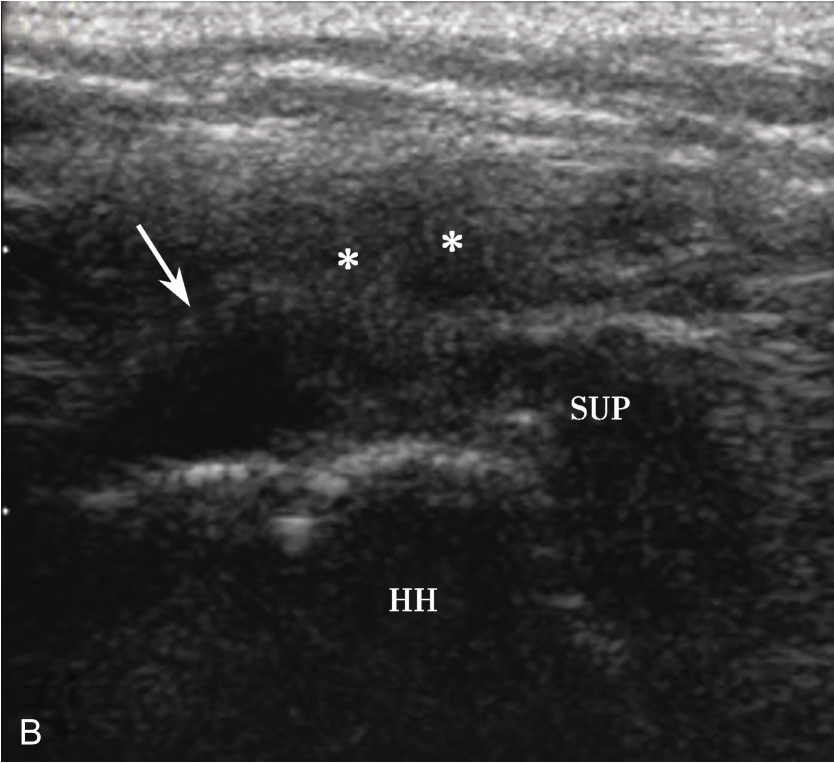

▲ 图2-1-8 超声引导下肩峰下-三角肌下滑囊造影图(一)

A.超声引导下滑囊内注入超声造影剂后,滑囊呈线状高增强(箭头);B.注入造影剂后的滑囊(箭头),冈上肌腱(SUP)连续性好,未见撕裂,HH:肱骨头